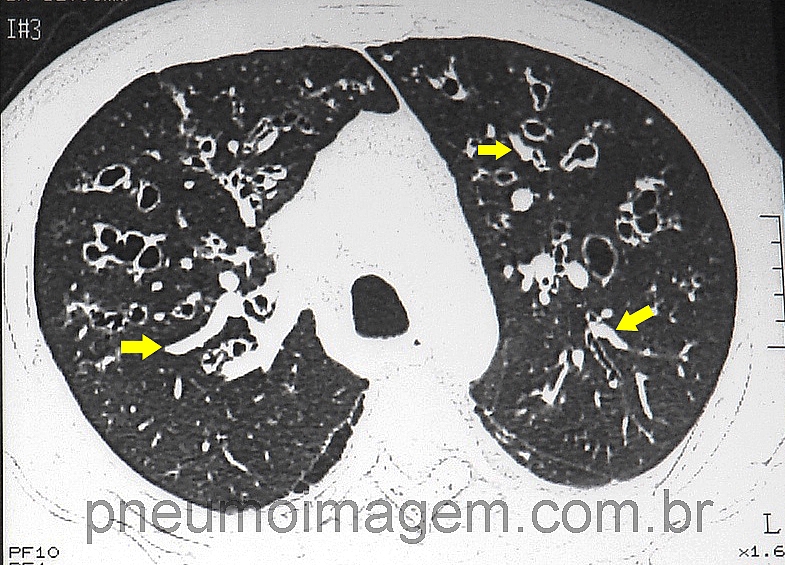

-AI provável: no mínimo um fator de risco para AI + no mínimo um achado tomográfico compatível com AI + Aspergillus sp no escarro ou lavado broncoalveolar (LBA); testes indiretos positivos (galactomanana no plasma, soro ou LBA.